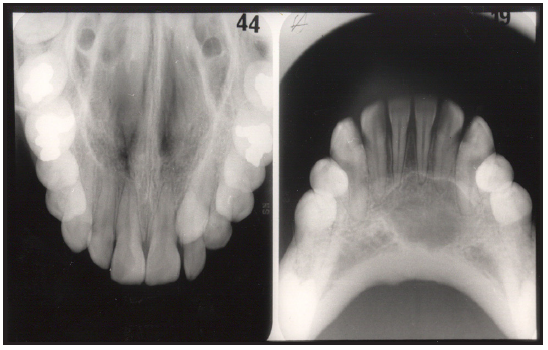

2. Center the receptor on the canine as close as possible to the lingual surfaces of the teeth, with approximately a one-eighth inch border of the receptor extending below the incisal edge of the teeth. (Figure 43) Position the biteblock on the incisal edges of the teeth to be radiographed. (Figure 44)

4. Align the central ray perpendicular to the bisector vertically and at the desired interproximal contact to be viewed. Horizontally, the central ray should bisect the canine. (Figure 45) For maxillary exposures, the tube head will be pointed down for positive (+) angulation.